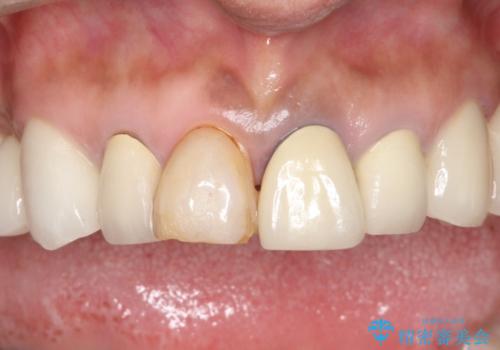

- 昔治療した前歯の色味が気になるとのことで来院されました。

昔に治療された前歯が変色しているのと、形態が自然ではありませんでした。

前歯2本をオールセラミックにすることにしました。